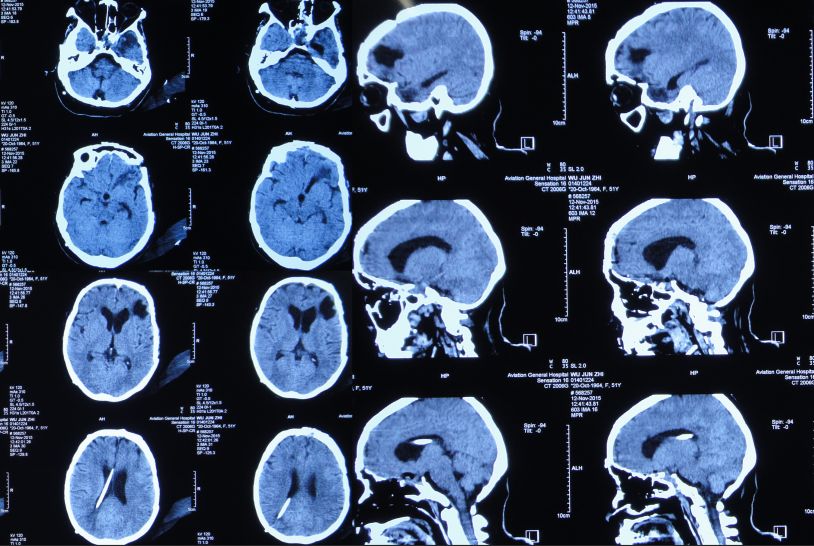

入院后第1天即2015年8月8日,复查头CT头:脑脊液蝶窦瘘征象。脑室扩张,双侧额叶片状密度减低,左侧额叶软化灶形成;脑沟、裂变浅;鞍上池及右侧脑室前角积气(图17)。

图17:2015年8月8日头CT:脑室扩张,鞍上池及右脑室前角积气